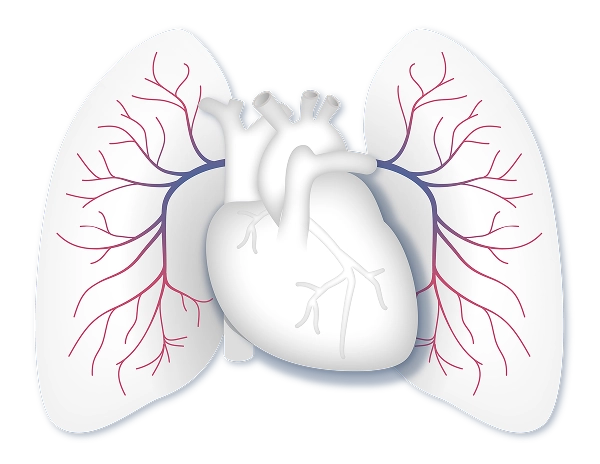

Echocardiogram (“Echo”)

Echo is a common, noninvasive test that uses soundwaves (ultrasound) to create an image of your heart to measure its size and shape and how well it squeezes and relaxes.

Echo can’t directly measure the pressure in your heart—that’s something only a right heart cath can do.

An Echo can indicate the need for a right heart cath to look more closely at the pressures in your right heart